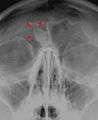

Osteoma of the frontal sinus seen on x-ray

Osteoma represents the most common benign neoplasm of the nose and paranasal sinuses. The cause of osteomata is uncertain, but commonly accepted theories propose embryologic, traumatic, or infectious causes. Osteomata are also found in Gardner's syndrome. Larger craniofacial osteomata may cause facial pain, headache, and infection due to obstructed nasofrontal ducts. Often, craniofacial osteoma presents itself through ocular signs and symptoms (such as proptosis).[1]